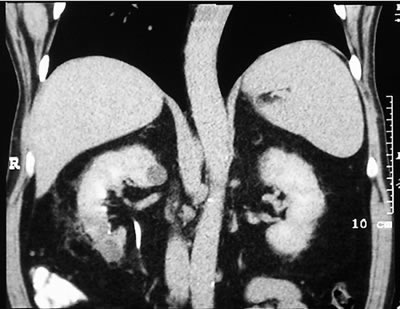

Мониторинг

(7 месяцев)

КТ легких – норма.

УЗИ брюшной полости – метастазов в печени нет. |

Спиральная

компьютерая томография (СКТ)

в нижнем сегменте образование

30х34х40 мм, располагающееся экстраренально, структура

неоднородна с наличием компонентов жировой плотности

по периферии, а также мягкотканой части.

|

в паранефральной клетчатке

- умеренные фиброзные изменения.